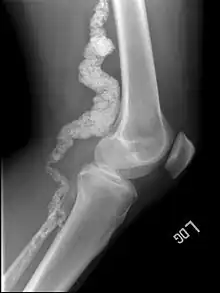

| A knee x-ray of a person with ACDC | |

Arterial calcification due to deficiency of CD73 (ACDC) is a rare genetic disorder that causes calcium buildup in the arteries and joints of the hands and feet, and other areas below the waist.[1] Although patients exhibiting these symptoms have been identified as early as 1914, this disorder had not been studied extensively until recently. The identification of the specific ACDC gene and mutations occurred in 2011. ACDC is caused by a mutation in the NT5E gene, which prevents calcium-removing agents from functioning,.[1][2] Patients with this mutation experience chronic pain, difficulty moving, and increased risk of cardiovascular problems.[1][2] In experiments at the molecular level, treatment with adenosine or a phosphatase inhibitor reversed and prevented calcification, suggesting they could be used as possible treatment methods.[1] There is currently no cure for ACDC, and patients have limited treatment options which focus primarily on removal of blood calcium and improving mobility.[1][2]